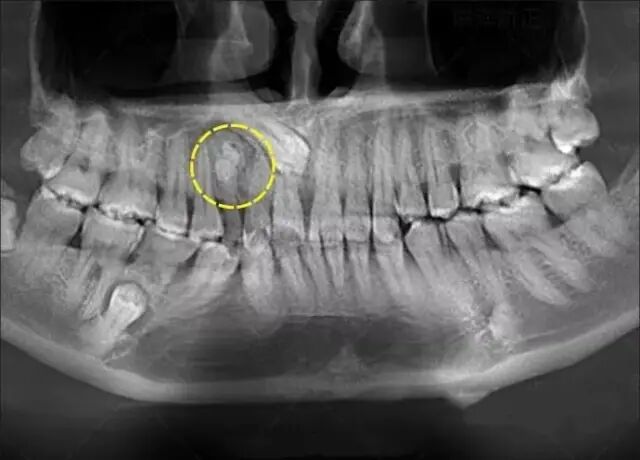

一般来说,常见的蛀牙通常可以通过牙片发现,尤其是龋坏比较多(如下图),在牙片上会出现黑色阴影的缺损。

因此,正是因为牙片拍摄及时,医生给予了正确的判断,在蛀牙初期便提前治疗,避免了越发严重的后果。

画圈圈的部分就说明牙齿已经在慢慢的龋齿化,慢慢的蛀坏!

曲面断层片怎么看科普知识:你会看牙片嘛?今天手把手教你看!_https://www.jmylbn.com_新闻资讯_第13张

暗的部位说明龋齿已经非常严重了!

下面这个是接近牙髓了。